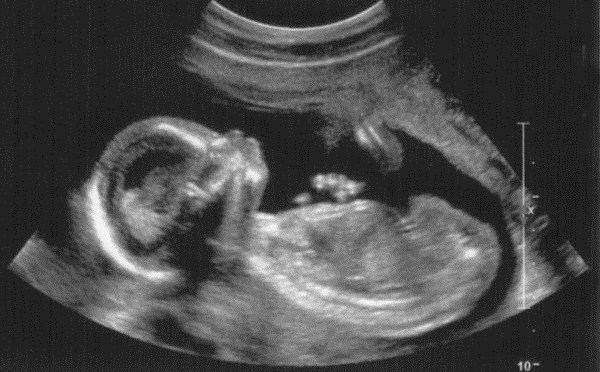

The Baby Dies

When my oldest son was 4 years old, we were on our way to “Life Chain”, a pro-life activity where everyone stood silently holding signs along the business route in support of life.  There were hundreds of people participating and the silence was, in and of itself, peaceful.

What I remember the most, however, was the drive.  Blake sat next to me and asked where we were going.  Thinking a short answer would suffice, I told him it was to support babies who hadn’t been born.  As kids will do, he filled his logic train by peppering me with, “Why?” over and over.

Honestly, I didn’t want him to know about abortion, but after answering a couple of questions vaguely, I let the word “abortion” slip out. He zeroed in like a heat seeking missile. Continue reading The Baby Dies